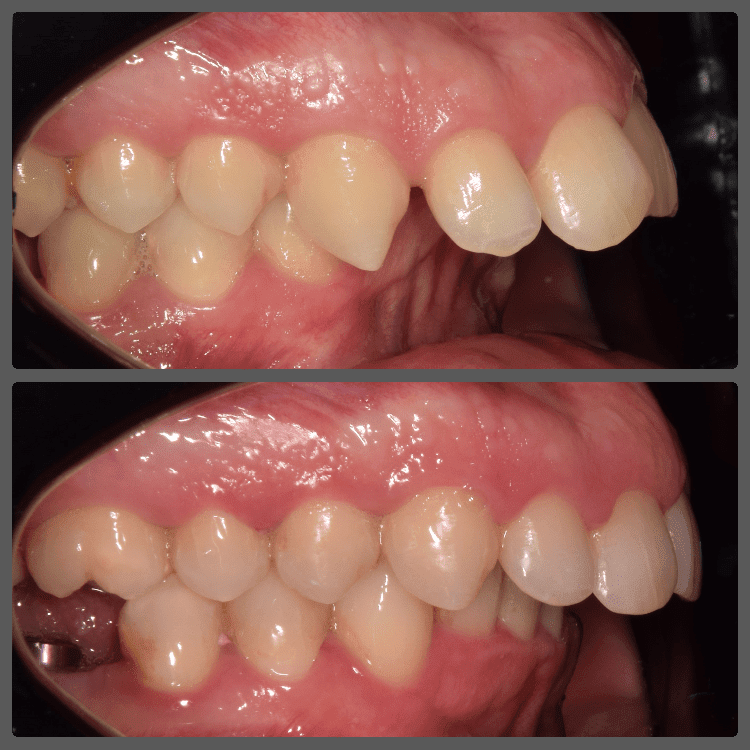

Balázs súlyos alsó torlódása miatt keresett fel magánrendelésemen. A diagnosztikus vizsgálatok során előbbin túl alsó-felső fogívszűkületet, valamint nyitott harapási hajlamot állapítottam meg. Kezelését Pitts21 alsó-felső rögzített fogszabályozó készülékkel kezdtük meg. A nyitott harapási hajlamot a hátsó fogakra helyezett harapásemelővel kontrolláltuk. A torlódott fogaknak tolórugóval és interproximális redukcióval teremtettünk helyet, és intermaxilláris gumihúzással tökéletesítettük a harapást. A fogszabályzó kezelés teljes időtartama alatt Balázs 110%-osan együttműködő volt, ezért 21 hónap alatt sikerült kiemelkedő végeredményt elérnünk.